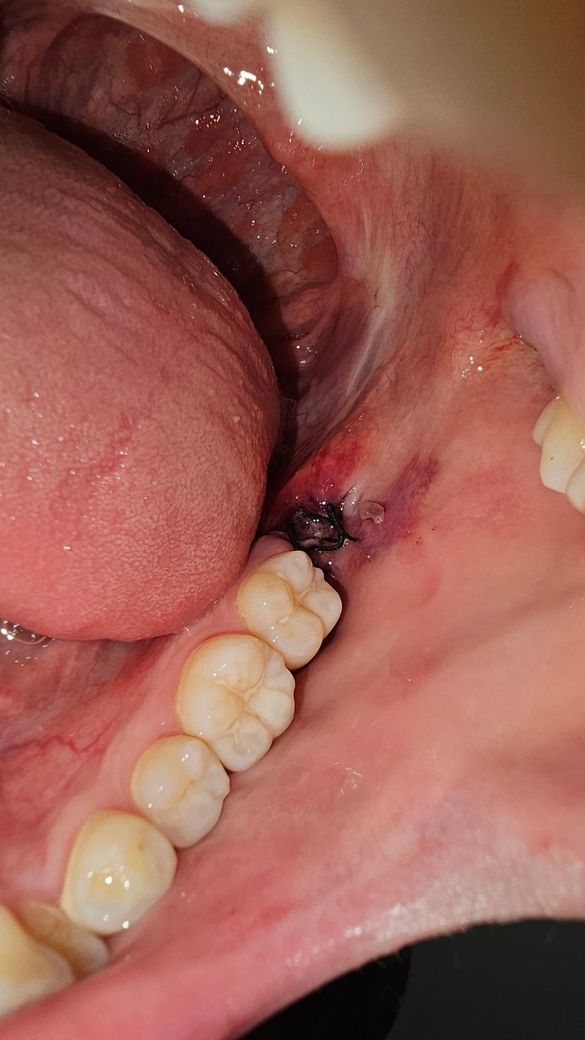

매복사랑니 발치 3일차인데 하얀색 점같은게있어요

안뇽하세요 매복사랑니 발치한지 3일차인데 아랫쪽에 뭔가 하얀색 점같은게 생겼는데 이거 음식물 찌거기인가요? 정상적으로 치유되고있는건가요?

• 1번 째 사진

1. 사랑니 발치 부위 옆의 볼쪽은 마취주사로 인한 것, 발치 중 기구에 눌려서 그런 것 같고요.

2. 발치 부위의 하얀색 점처럼 생긴 것은 단순 이물질 같습니다. 살살 가글해서 위생관리 해주세요.